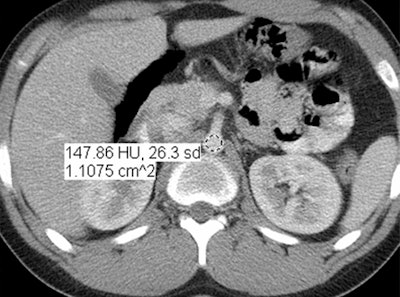

In an objective evaluation, reduced-dose MBIR images had decreased image noise compared with standard-dose 30% ASIR images (for example, 12.7 HU versus 19.4 HU in the aorta, respectively, and 8.7 HU versus 14.2 HU in the liver).